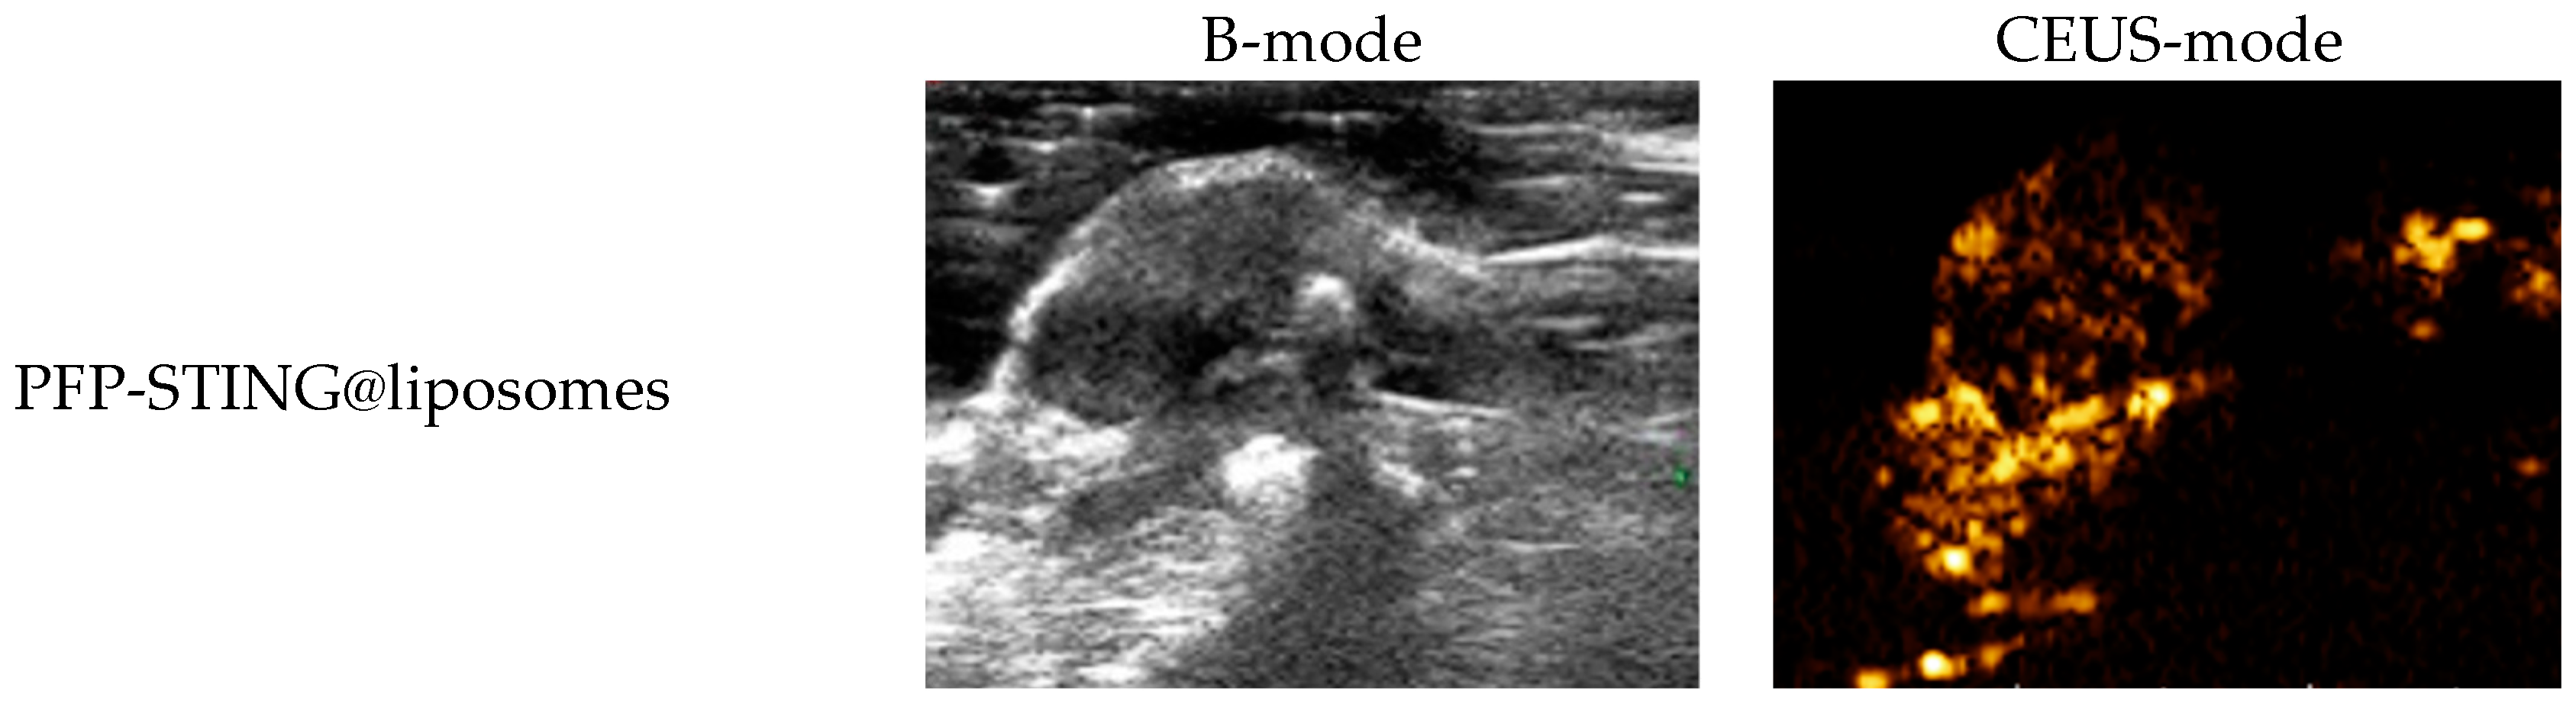

The ultrasound imaging of both targeted and non-targeted liposomes pre-ultrasound irradiation revealed no significant difference in US signal intensity between the two groups in both B- and CEUS-modes (p > 0.05) as shown in Figure 3. These images were captured using a US system (Esaote MyLab90, Florence, Italy) with the imaging parameters set to MI 0.08, TIB 0.3, and probe type LA523. Two factors were considered to induce the transition of liposomes into bubbles: heating (thermal factor) and ultrasound treatment (mechanical factors). The core of the nanodroplets used in this study was PFP, which has a boiling point of 29 °C at atmospheric pressure. However, according to Laplace pressure principles, droplets encapsulated in lipid shells can stabilize larger droplets and withstand greater pressure, which contributes to an increased evaporation temperature of the droplets [51,52]. This phenomenon suggests that nanodroplets facilitate infiltration into tumor tissues in vivo, enabling effective ultrasound imaging beyond the boundaries of tumor blood vessels. Therefore, they can enhance spatial contrast signals in both B-mode and CEUS-mode. The ADV was fixed at an ultrasound irradiation time of 3 min and an irradiation intensity of 3 W [38]. Following ultrasound irradiation, the liposomes underwent effective vaporization for ultrasound imaging, demonstrating the feasibility of using ADV simultaneously for both imaging and treatment purposes.

Figure 3.

(a) B-mode and CEUS-mode ultrasound images of PFP-STING@liposomes and iRGD-PFP-STING@liposomes before and after LIFU irradiation with 3 W for 3 min. Scale bar: 5 mm. (b) Echo intensity values of liposomes irradiated using LIFU. Data are represented as the mean ± SEM (n = 3, * p < 0.05, *** p < 0.001).

In Vivo Ultrasound Imaging

To evaluate the contrast-enhanced ultrasound effect of the liposomes in vivo, ultrasound imaging experiments were conducted on mice bearing 4T1 breast cancer xenografts. Following the injection of liposomes and subsequent ultrasound irradiation, a significant enhancement of the ultrasound signal was observed in the tumor region in both B-mode and CEUS-mode. Figure 5 illustrates the ultrasound images of the liposomes after destruction. Following 10 min of injection, exposure to LIFU at 3 W/cm2 in pulsed wave mode for three minutes resulted in the formation of hyperechoic regions in the tumor, as observed in both B-mode and CEUS-mode images. This finding indicated that phase transition of the nanoliposomes was successfully induced through ADV. In CEUS-mode, the ultrasound signal intensity in tumors treated with targeted iRGD liposomes was higher compared to non-targeted tumors. These results demonstrated that the developed liposomes enabled real-time monitoring and visualization of the tumor treatment area during drug therapy. In addition, the results confirmed that these liposomes exhibited targeted anti-tumor activity and could be effectively employed for ultrasound imaging, representing a promising therapeutic approach for tumor targeting.

Figure 5.

In vivo ultrasound imaging. The US and CEUS imaging pictures of PFP-STING@liposomes and iRGD-PFP-STING@liposomes obtained at 13 min post-injection. LIFU was applied for 3 min in 4T1 breast cancer xenograft model mice.